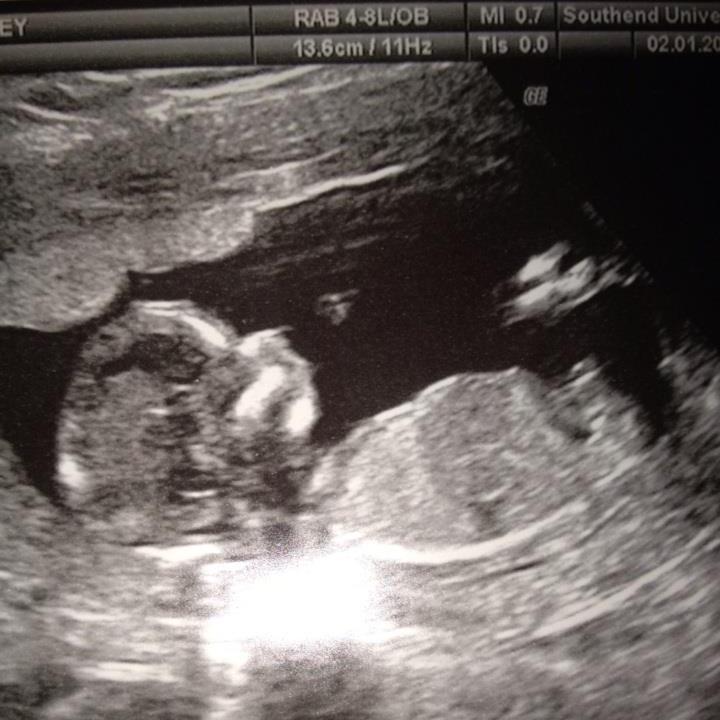

Guesses please? 13+ 4. Thankyou. x